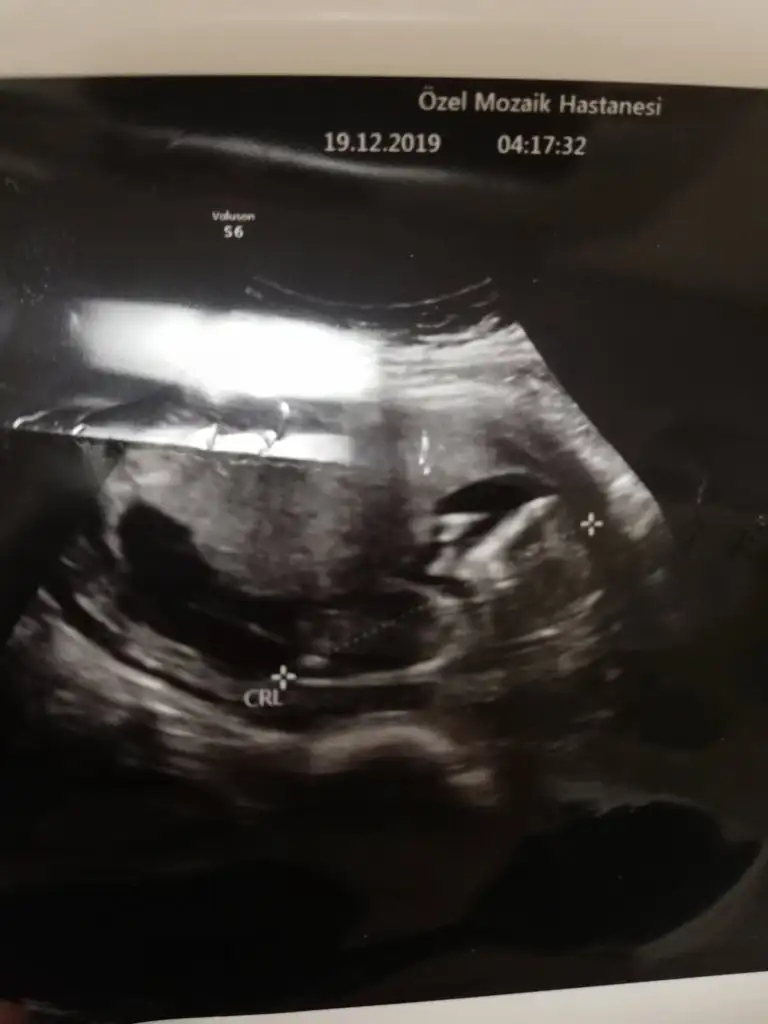

Merhaba kizlar Dr dan geldim devlet hastanesi olunca 10 sn ultrasonda anca baktı sormadım bende cinsiyeti falan ama kendi drma gidince sorucam kan falan verdim yorum yapabilecek varsa resmi atıyorum , nuba falan 😄12 hafta 6 günlük çıktı el salladı bana 😁Eki Görüntüle 2566468 Eki Görüntüle 2566469

Canım nub fotografı almamış tahmin yapmak çok zor ama skull teorisine göre erkek. Skull teorisi kemik yapısına göre cinsiyet tahmini dedikleri şey. Genital çıkıntıya değil kafa tası, çene kemiğine vs bakılıyor. Gerçi skull nuba göre daha fazla yanılıyor. Yine de çok iyi bir erkek skull örneği minnoş kafası :)

Benimde şimdi kontrol vardı 2li için kan verdim ense kalınlığı çene kemiği burun çok iyi dedi Dr. hatta 12+5 im 13+1 göründü. Çok şükür. Cinsiyet öğrenirim diye bir heyecanla geldim ama 1 ay sonra dedi sadece başından beri erkeğe benziyor diyo. Ultrason fotolarımızı koydum ama Nubu çıkmamış heralde. Gelde 1 ay dayan şimdi. ☺️

Benimde şimdi kontrol vardı 2li için kan verdim ense kalınlığı çene kemiği burun çok iyi dedi Dr. hatta 12+5 im 13+1 göründü. Çok şükür. Cinsiyet öğrenirim diye bir heyecanla geldim ama 1 ay sonra dedi sadece başından beri erkeğe benziyor diyo. Ultrason fotolarımızı koydum ama Nubu çıkmamış heralde. Gelde 1 ay dayan şimdi. ☺

Canım ben sende ne nub ne skull görebildim ikisi de net değil :( zaten yeni yeni aradaki farkları görmeye başladım belki iyi bilen biri anlar.